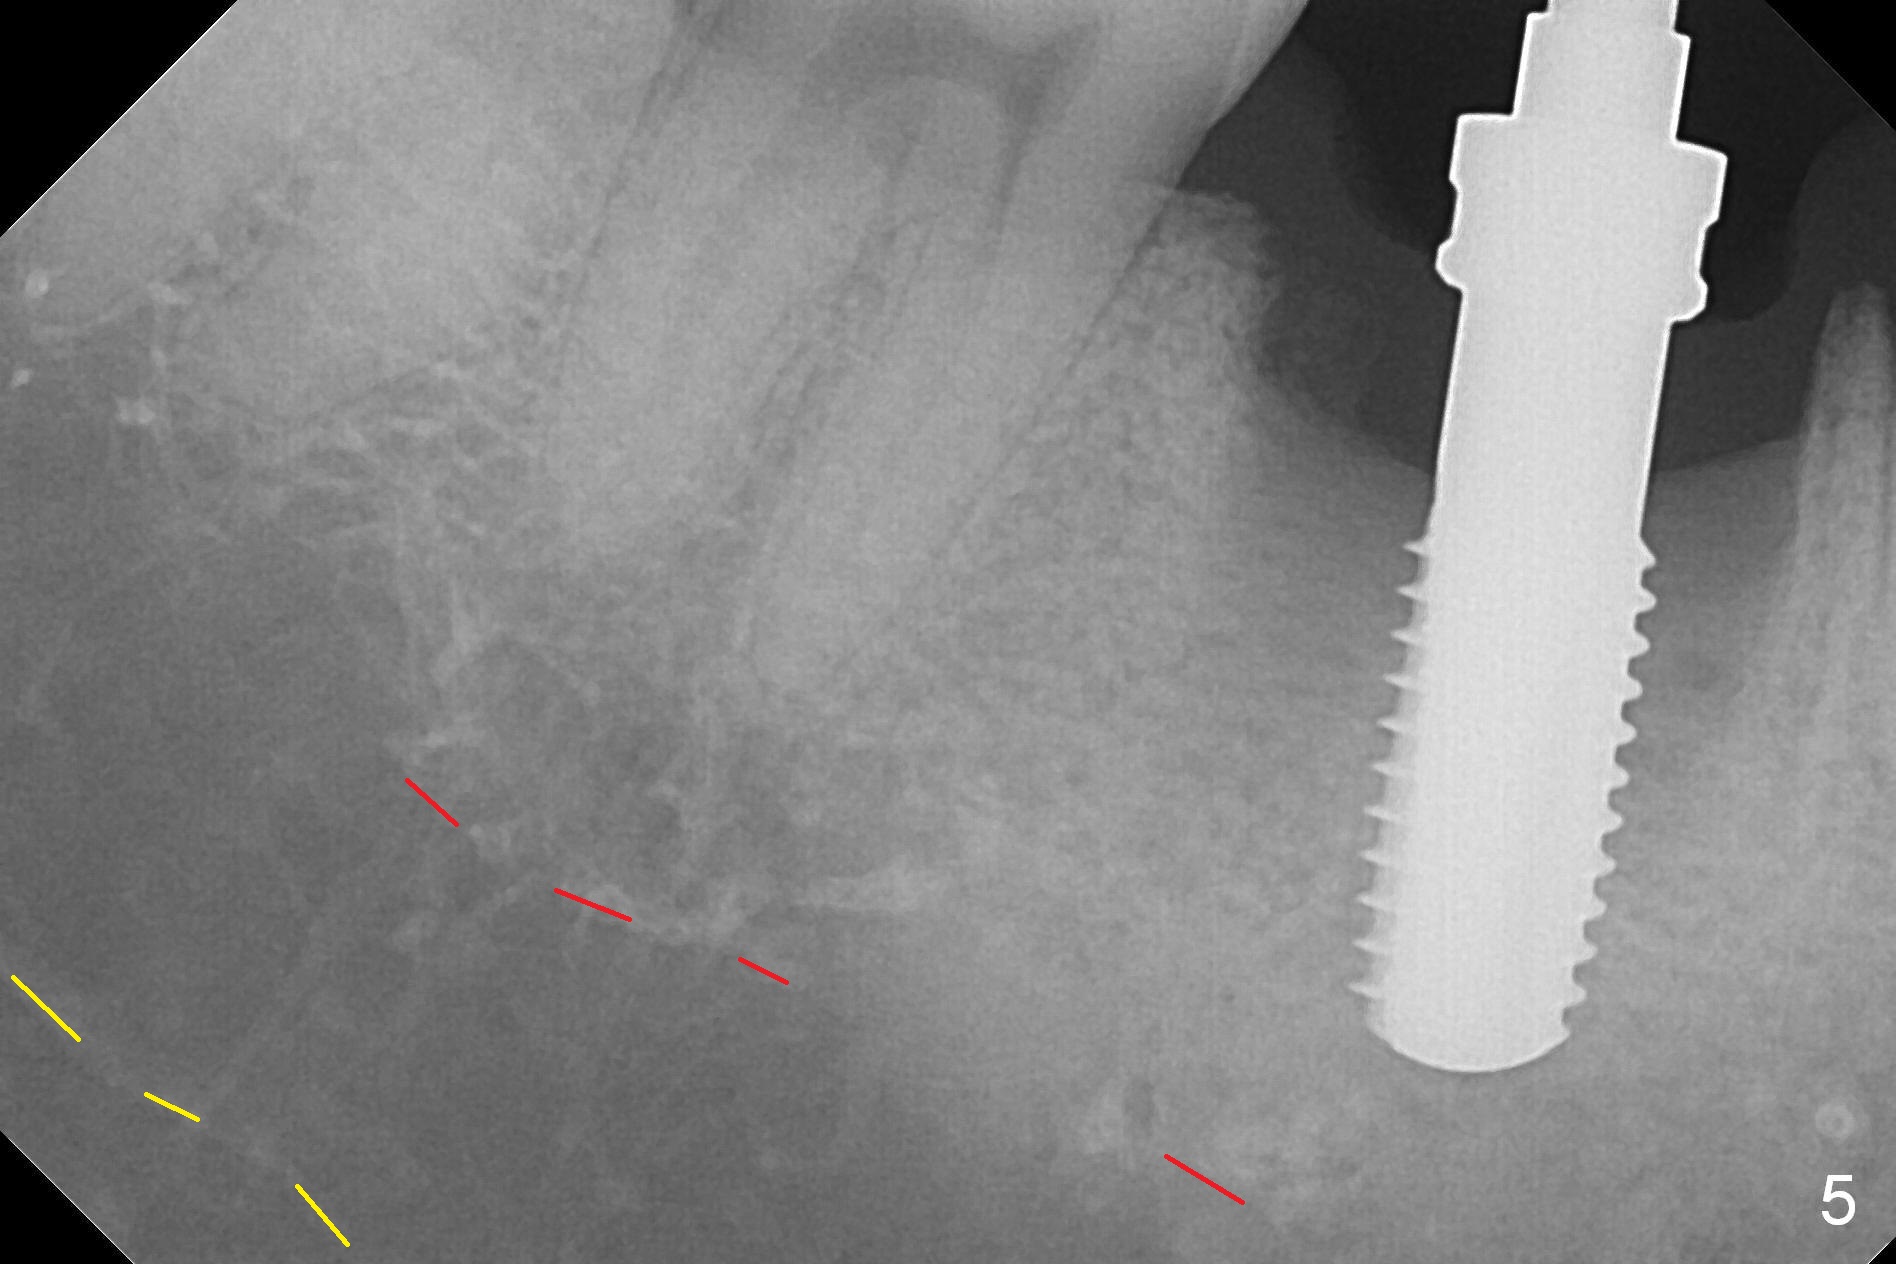

After extraction of the tooth #30 with Class V furcation involvement (Fig.1 (>),2 (L: lingual)), initial osteotomy depth is 8 mm with infiltration anesthesia, but a parallel pin is able to be inserted for 16 mm without pain (Fig.3). There is oozing from the osteotomy. Osteotomy increases in diameter with depth at 8 mm (Fig.4 (3.8 mm drill),5 (5.3 mm tap)). As the Inferior Alveolar Canal (IAC) is indistinct with increased pain during osteotomy, a 5.9x6 mm implant is placed with >50 Ncm following Septocaine infiltration (Fig.6). When bone graft (Fig.7 *) and 7.8x5.5(6) mm abutment (Fig.7,8) are placed, panoramic X-ray is taken (Fig.9). There appears to be a thick layer of spongy bone in the posterior mandible between the red and yellow dashed lines (Fig.5,9). Panoramic X-ray and/or CBCT should be taken if preop PA does not reveal IAC. This patient seems to be a bruxer. There are mandibular tori. Bone loss (furcation involvement) is not proportional to his oral hygiene status. Functional loading (progressive) should be delayed due to bruxism and the short implant.